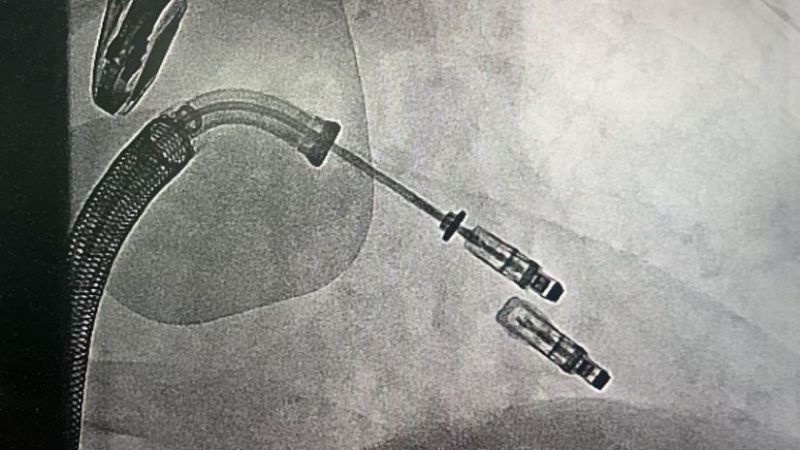

手術(shù)于11月4日下午進(jìn)行,通過股靜脈穿刺送入夾合器,在食道超聲實(shí)時(shí)引導(dǎo)下,精準(zhǔn)植入2枚瓣膜夾修復(fù)二尖瓣。整個(gè)過程歷時(shí)約2小時(shí),術(shù)中出血量?jī)H50ml。術(shù)后次日,患者即可下床活動(dòng),復(fù)查顯示EF提升至46%,二尖瓣返流面積縮小至3.0cm2,左心房縮小至66mm,胸悶、氣短癥狀明顯緩解。

2.精準(zhǔn)定位:在食道超聲和X線引導(dǎo)下,將夾合器送達(dá)二尖瓣位置,通過夾合病變瓣膜減少返流;